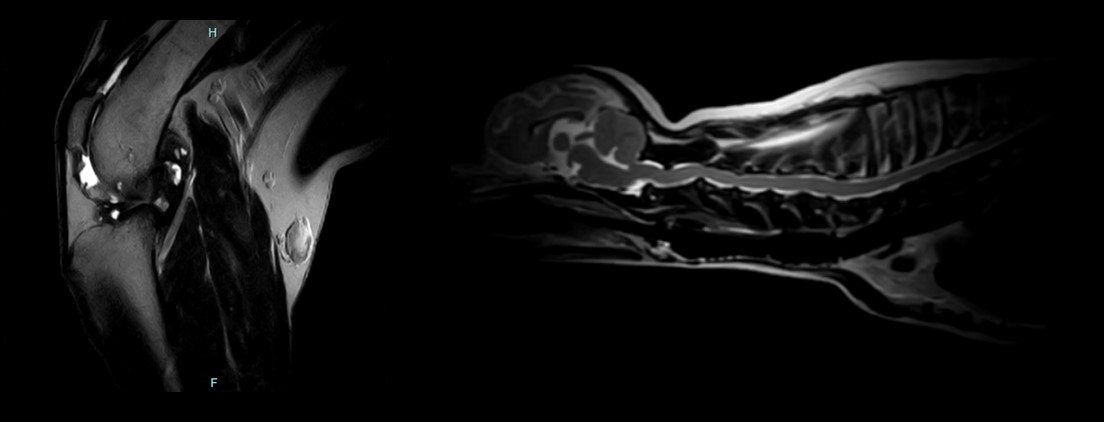

APERTO Lucent VET’s wide, laterally moving table and wide selection of high-sensitivity coils enable effective imaging across a broad range of animal sizes and body shapes. The open magnet design accommodates support equipment and in-place interventional procedures.

• Single-pillar design for maximum access and positioning flexibility

• Lateral table shift simplifies precise positioning and workflow